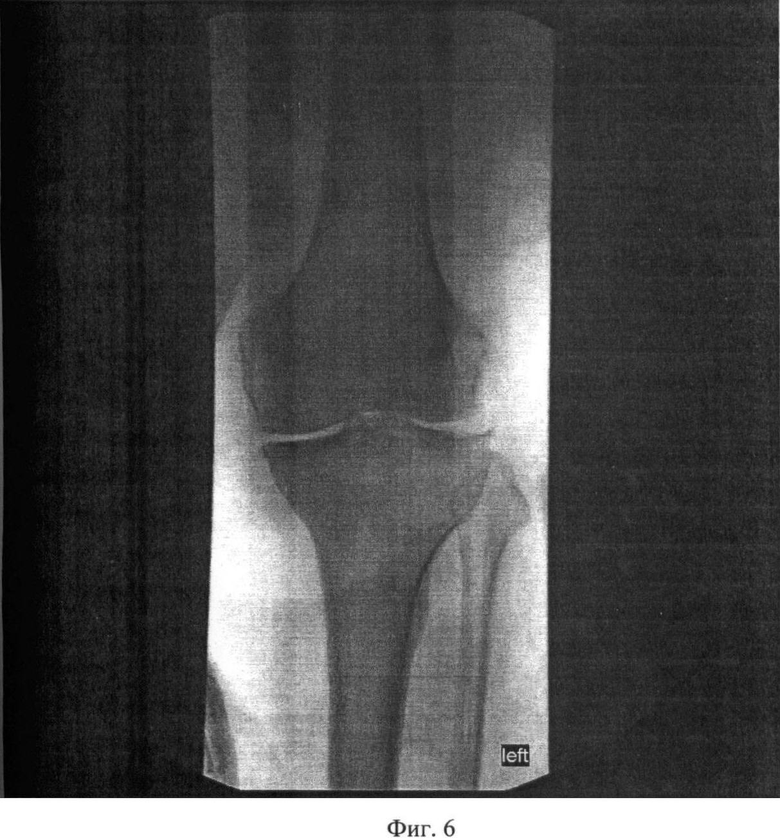

Рекурвация коленного сустава: рентгеновские снимки и объяснения